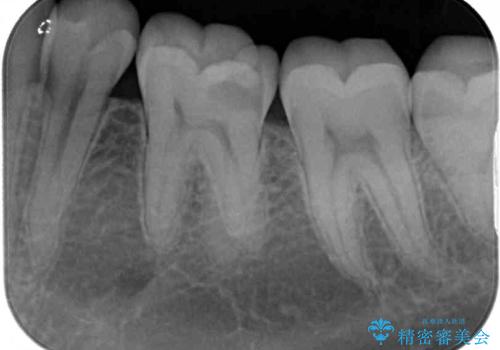

- 下顎左右奥歯に虫歯で痛みを感じるとのことで来院された患者様です。

むし歯が大きく、神経を取り除く可能性があることを理解いただいた上で虫歯を取り除き、その後はオールセラミッククラウンにて補綴することとしました。